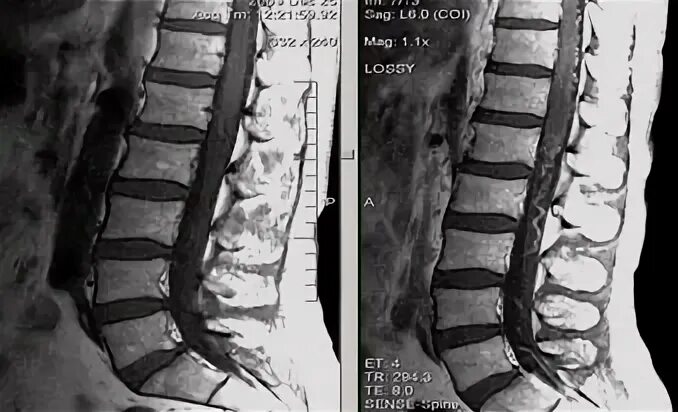

Деформация дурального мешка поясничного